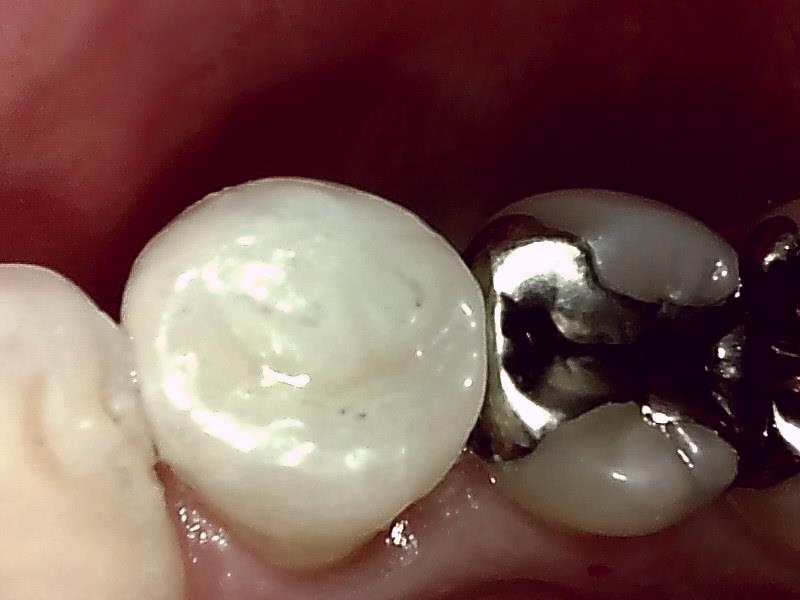

写真; セラミックインレー装着後の歯冠の仕上がり(咬合面観)